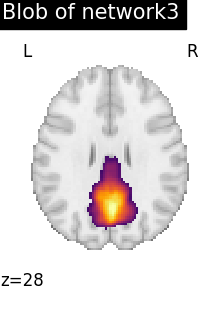

# To reduce the complexity, we choose to display all the regions

# extracted from network 3

regions_indices_network3 = np.where(np.array(extraction.index_) == 3)

for index in regions_indices_network3[0]:

cur_img = index_img(extraction.regions_img_, index)

coords = find_xyz_cut_coords(cur_img)

plotting.plot_stat_map(

cur_img,

display_mode="z",

cut_coords=coords[2:3],

title="Blob of network3",

colorbar=False,

cmap="inferno",

vmax=15,

)